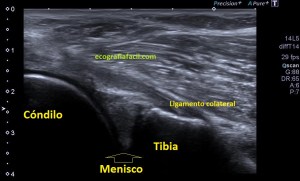

La valoración de los meniscos no suele ser realizada de modo habitual por ecografía como primera técnica de elección.

Lo primero de todo es saber cómo debemos ver un menisco en la ecografía, para ello debemos buscar la cara lateral, interna o externa que deseemos estudiar, con sonda lineal de alta frecuencia, corte longitudinal o eje largo respecto de la rodilla a estudio, es decir, como si hiciésemos un corte coronal de la misma.

Que debemos encontrar, bien, algo parecido a esto:

Esta es la normalidad, es una imagen preciosa cedida por Javier Álvarez @fisioequilibra, TSID, Fisioterapeuta, Profesor de la Universidad Francisco de Vitoria de Madrid, colaborador del Blog y amigo de los que se cuentan con los dedos de la mano…

Es lo primero que debes buscar, es lo más importante. En la imagen  1 puedes ver un menisco normal y sano, señalado por la flecha hueca amarilla. Semiológicamente es una estructura cónica hiperecogénica, homogénea en la cara externa de la rodilla entre la tibia y el cóndilo femoral, profundo al ligamento colateral, es la parte visible del menisco por ecografía y es tu objetivo en cada exploración de esta zona.

En el caso de hoy, el paciente presentaba una imagen de la zona descrita en la imagen 1 y que ves la imagen siguiente que difiere significativamente de la normalidad.

2

En esta imagen vemos la misma región que viste en la imagen 1, donde claramente ves alterada la semiología de la ecoarquitectura de menisco, heterogéneo, hundido, y en la superficie del mismo, imágenes hipecogénicas muy finas que pueden indicar afectación del mismo. Un poco más superficial e indicado con la flecha roja observas una estructura anecoica, correspondiente a líquido que luego verás en detalle en fotos posteriores.